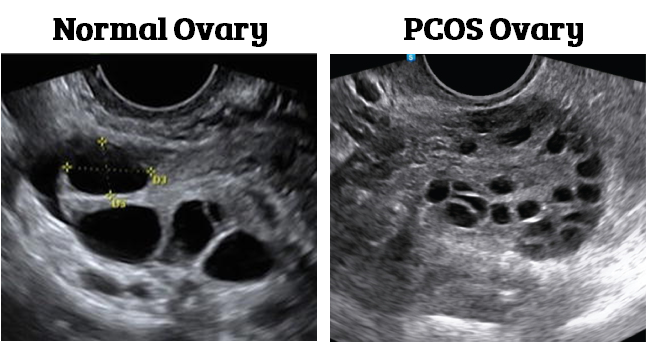

多囊卵巢综合症(PCOS)

与没有多囊卵巢综合症的妇女相比,患有多囊卵巢综合症的妇女不孕的情况大约是其10倍(Hart等人,2015)。

多囊卵巢综合症通常由(El Hayek等人,2016)诊断。

高雄激素症(男性性激素如睾酮的分泌增加月经周期不规律多囊卵巢(通过超声测量),其特点是有许多小卵泡

在多囊卵巢综合症中,较高的雄性激素水平破坏了参与卵泡发育的激素平衡。这导致了大量较小的、发育不良的卵泡(Dumesic等人,2008年)。

这些较小的卵泡可能不会以同样的速度发育,这可能会影响质量。Chen等人(2008年)发现,患有多囊卵巢综合症的妇女有。

取到更多的卵子,但成熟的卵母细胞较少较低的施肥量较少的高等级胚胎生活方式因素和卵子质量压力Ebbesen等人(2009年)研究了IVF前12个月发生的与较少怀孕和取回卵细胞有关的负面生活事件的数量。